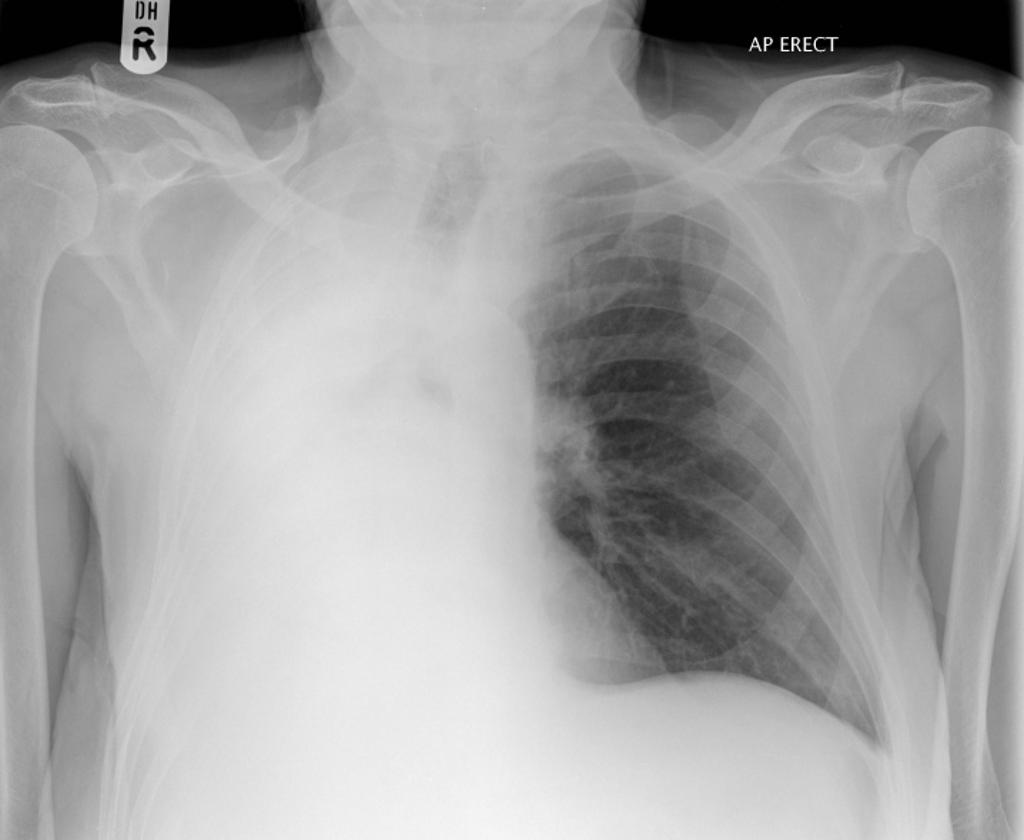

White Out